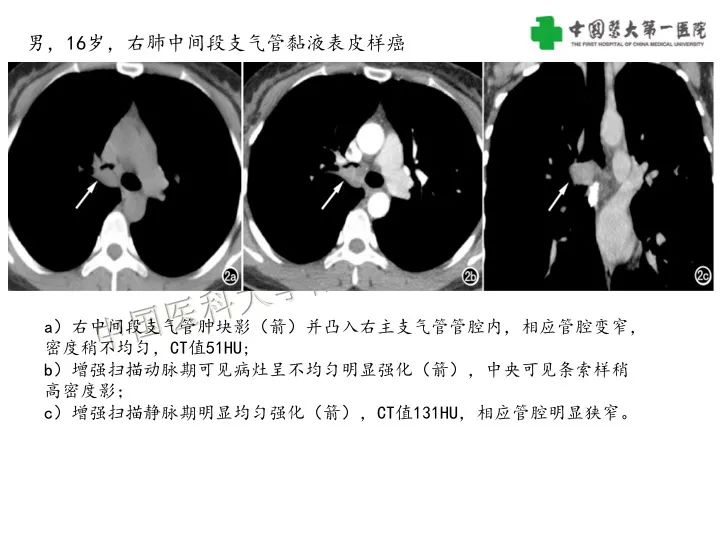

【病例】气管腺样囊性癌1例CT影像-1

【病例】气管腺样囊性癌1例CT影像-2

【病例】气管腺样囊性癌1例CT影像-3